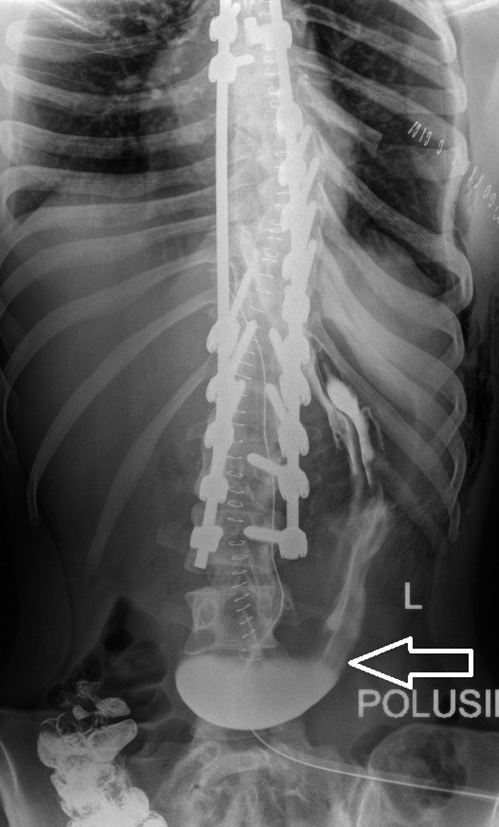

X-ray control was performed with the administration of a contrast agent through the duodenal probe (Fig. 4), which revealed restriction of the proximal distribution of the contrast agent with a clear, even vertical border at the level of the middle part of the horizontal loop of the duodenum.

Fig. 4. X-ray of the abdominal organs with the introduction of contrast through the duodenal probe